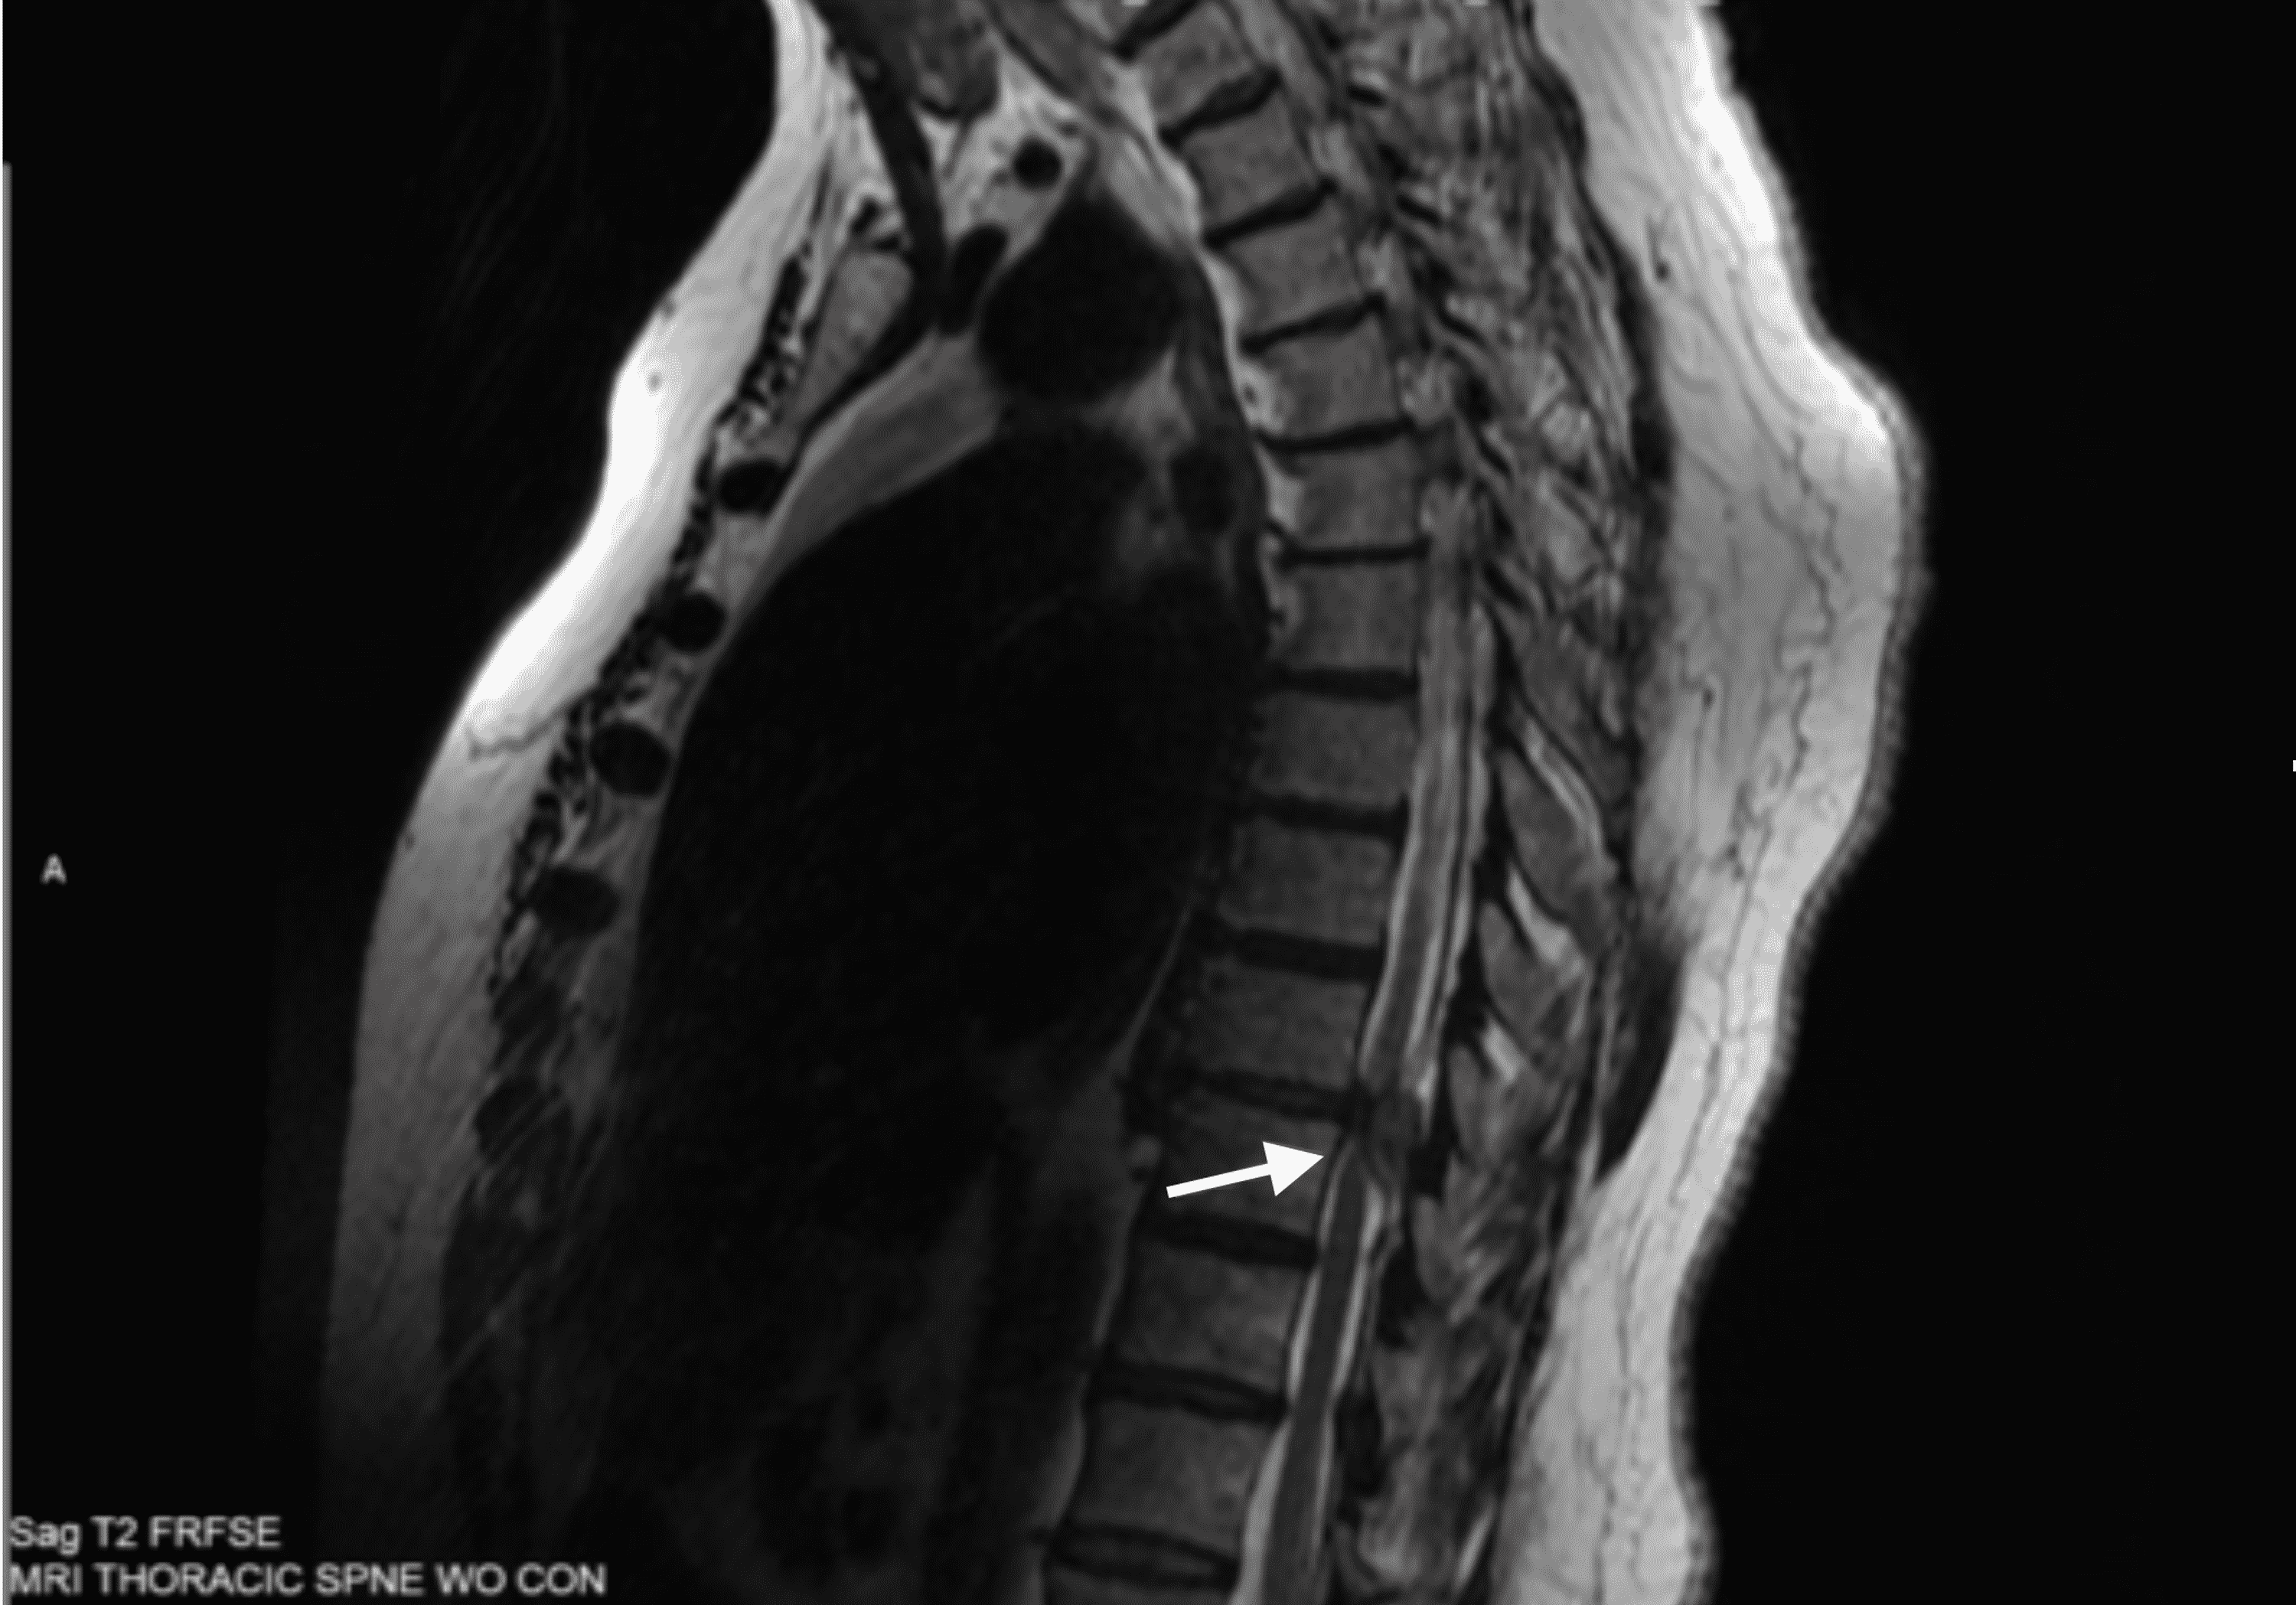

Herniated Disc Thoracic Mri

Herniated Disc Thoracic Mri Herniated Disc Neck Epidural  A cervical epidural injection is a safe and effective minimally invasive treatment for neck pain. This type of spinal injection made in the neck region. Slipped (herniated) disc medically reviewed by william morrison, m.d. Nerve root compression from either cervical spinal stenosis or a herniated disc of the cervical vertebra is the most common cause of cervical radiculopathy. If you. Herniated Disc Neck Epidural.